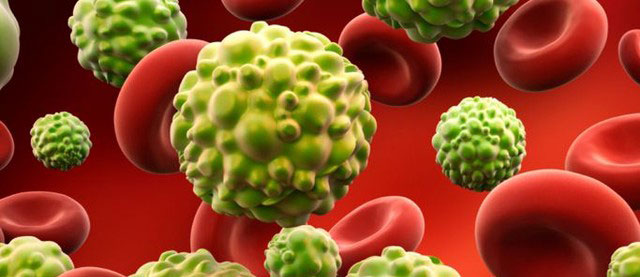

Vücudumuzda bulunan tüm organ ve dokular bir düzen içinde çalýþýr. Bunlarý oluþturan hücreler de benzer þekilde belirli bir düzen içinde büyür, bölünerek çoðalýr ve ölür. Vücudumuzdaki normal hücrelerin çoðalmasý sýrasýnda kontrol mekanizmalarýnýn kaybolmasý anormal hücrelerin oluþmasýna neden olur. Kontrol dýþý çoðalma gösteren, çevre dokulara ve uzak organlara yayýlma özelliði gösteren anormal hücre topluluklarýna genel olarak kanser denir.